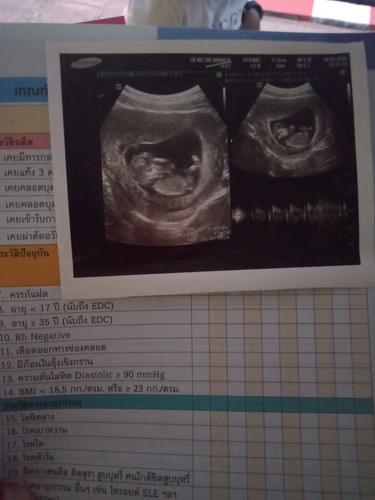

12 W 4 D

ตรวจเมื่อวานขึ้น 2 ขีด เลยมั้นใจว่าตัวเองท้อง เลยไปฝากครรภ์ ผลคือ 12W 4D ตกใจมากค่ะ เพราะที่ผ่านมา ปจด.ไม่มาไม่ได้เอะใจอะไร เพราะเคยปจด.ไม่มาเดือนกว่า แล้วที่ผ่านเกือบ2 เดือน ไม่มีอาการเหมือนคนท้อง ไม่อาเจียน มีแค่เวียนหัวบ้าง เพราะคิดว่าอากาศร้อน สรุปวันนี้ผลออกมา มีน้องแล้วจ้า รอลุ้นเพศต่อไปจ้า ??